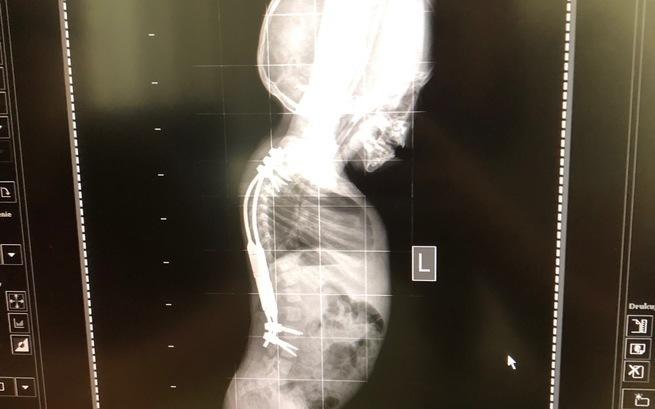

W ubiegłe wakacje Adaś przeszedł bardzo skomplikowaną operację kręgosłupa, spędziliśmy w szpitalu ponad 6 tygodni. Najpierw prostowaliśmy kręgosłup na specjalnie przygotowanym wyciągu z obręczą HALO a następnie został wszczepiony system prętów, które przez jakiś czas będą rozły razem z Adasiem. Rezultaty są świetne. Tę operację udało nam się sfinansować we współpracy z NFZ.